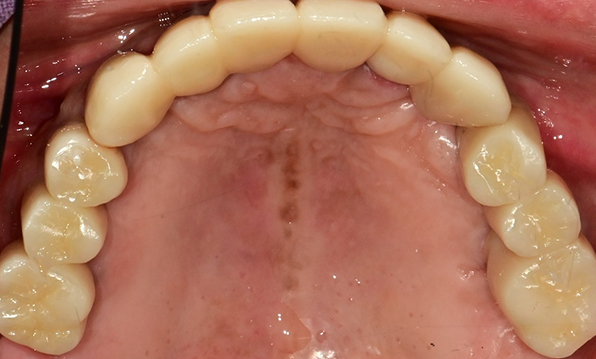

Before & After

Case 01

Before After